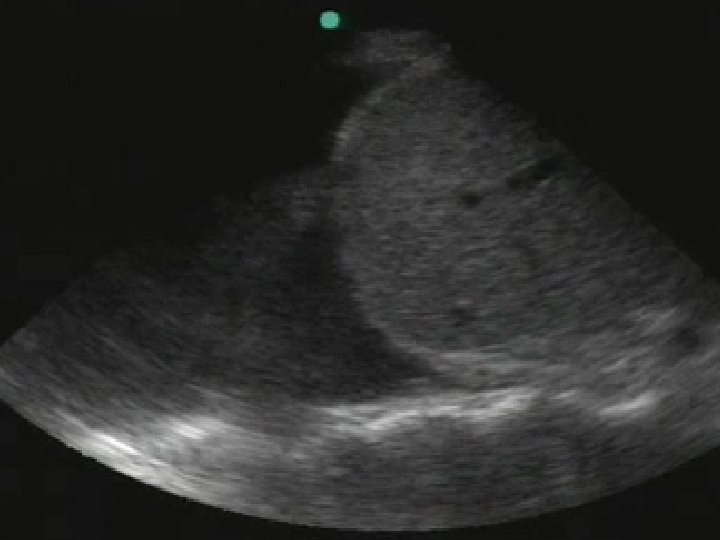

Pericardial • Transducer placed in sub-xiphoid region with beam projecting in coronal plane

Subcostal Liver RV LV